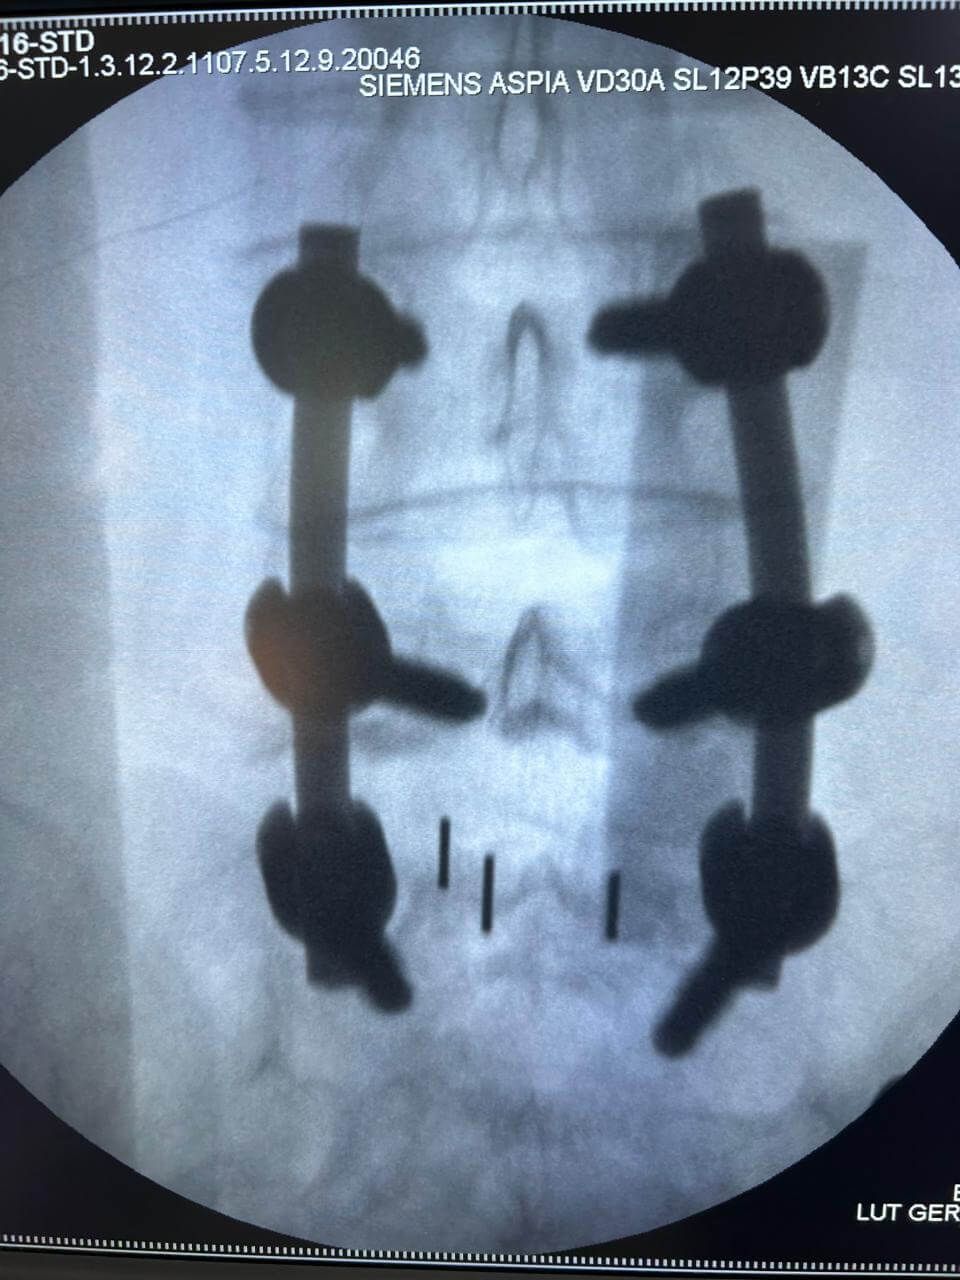

Cirugía de mínima invasión de columna vertebral

Realiza cirugías endoscópicas mínimamente invasivas de columna.

Cirugía de Columna

Realiza cirugía habitual y endoscópica mínimamente invasiva de columna vertebral.